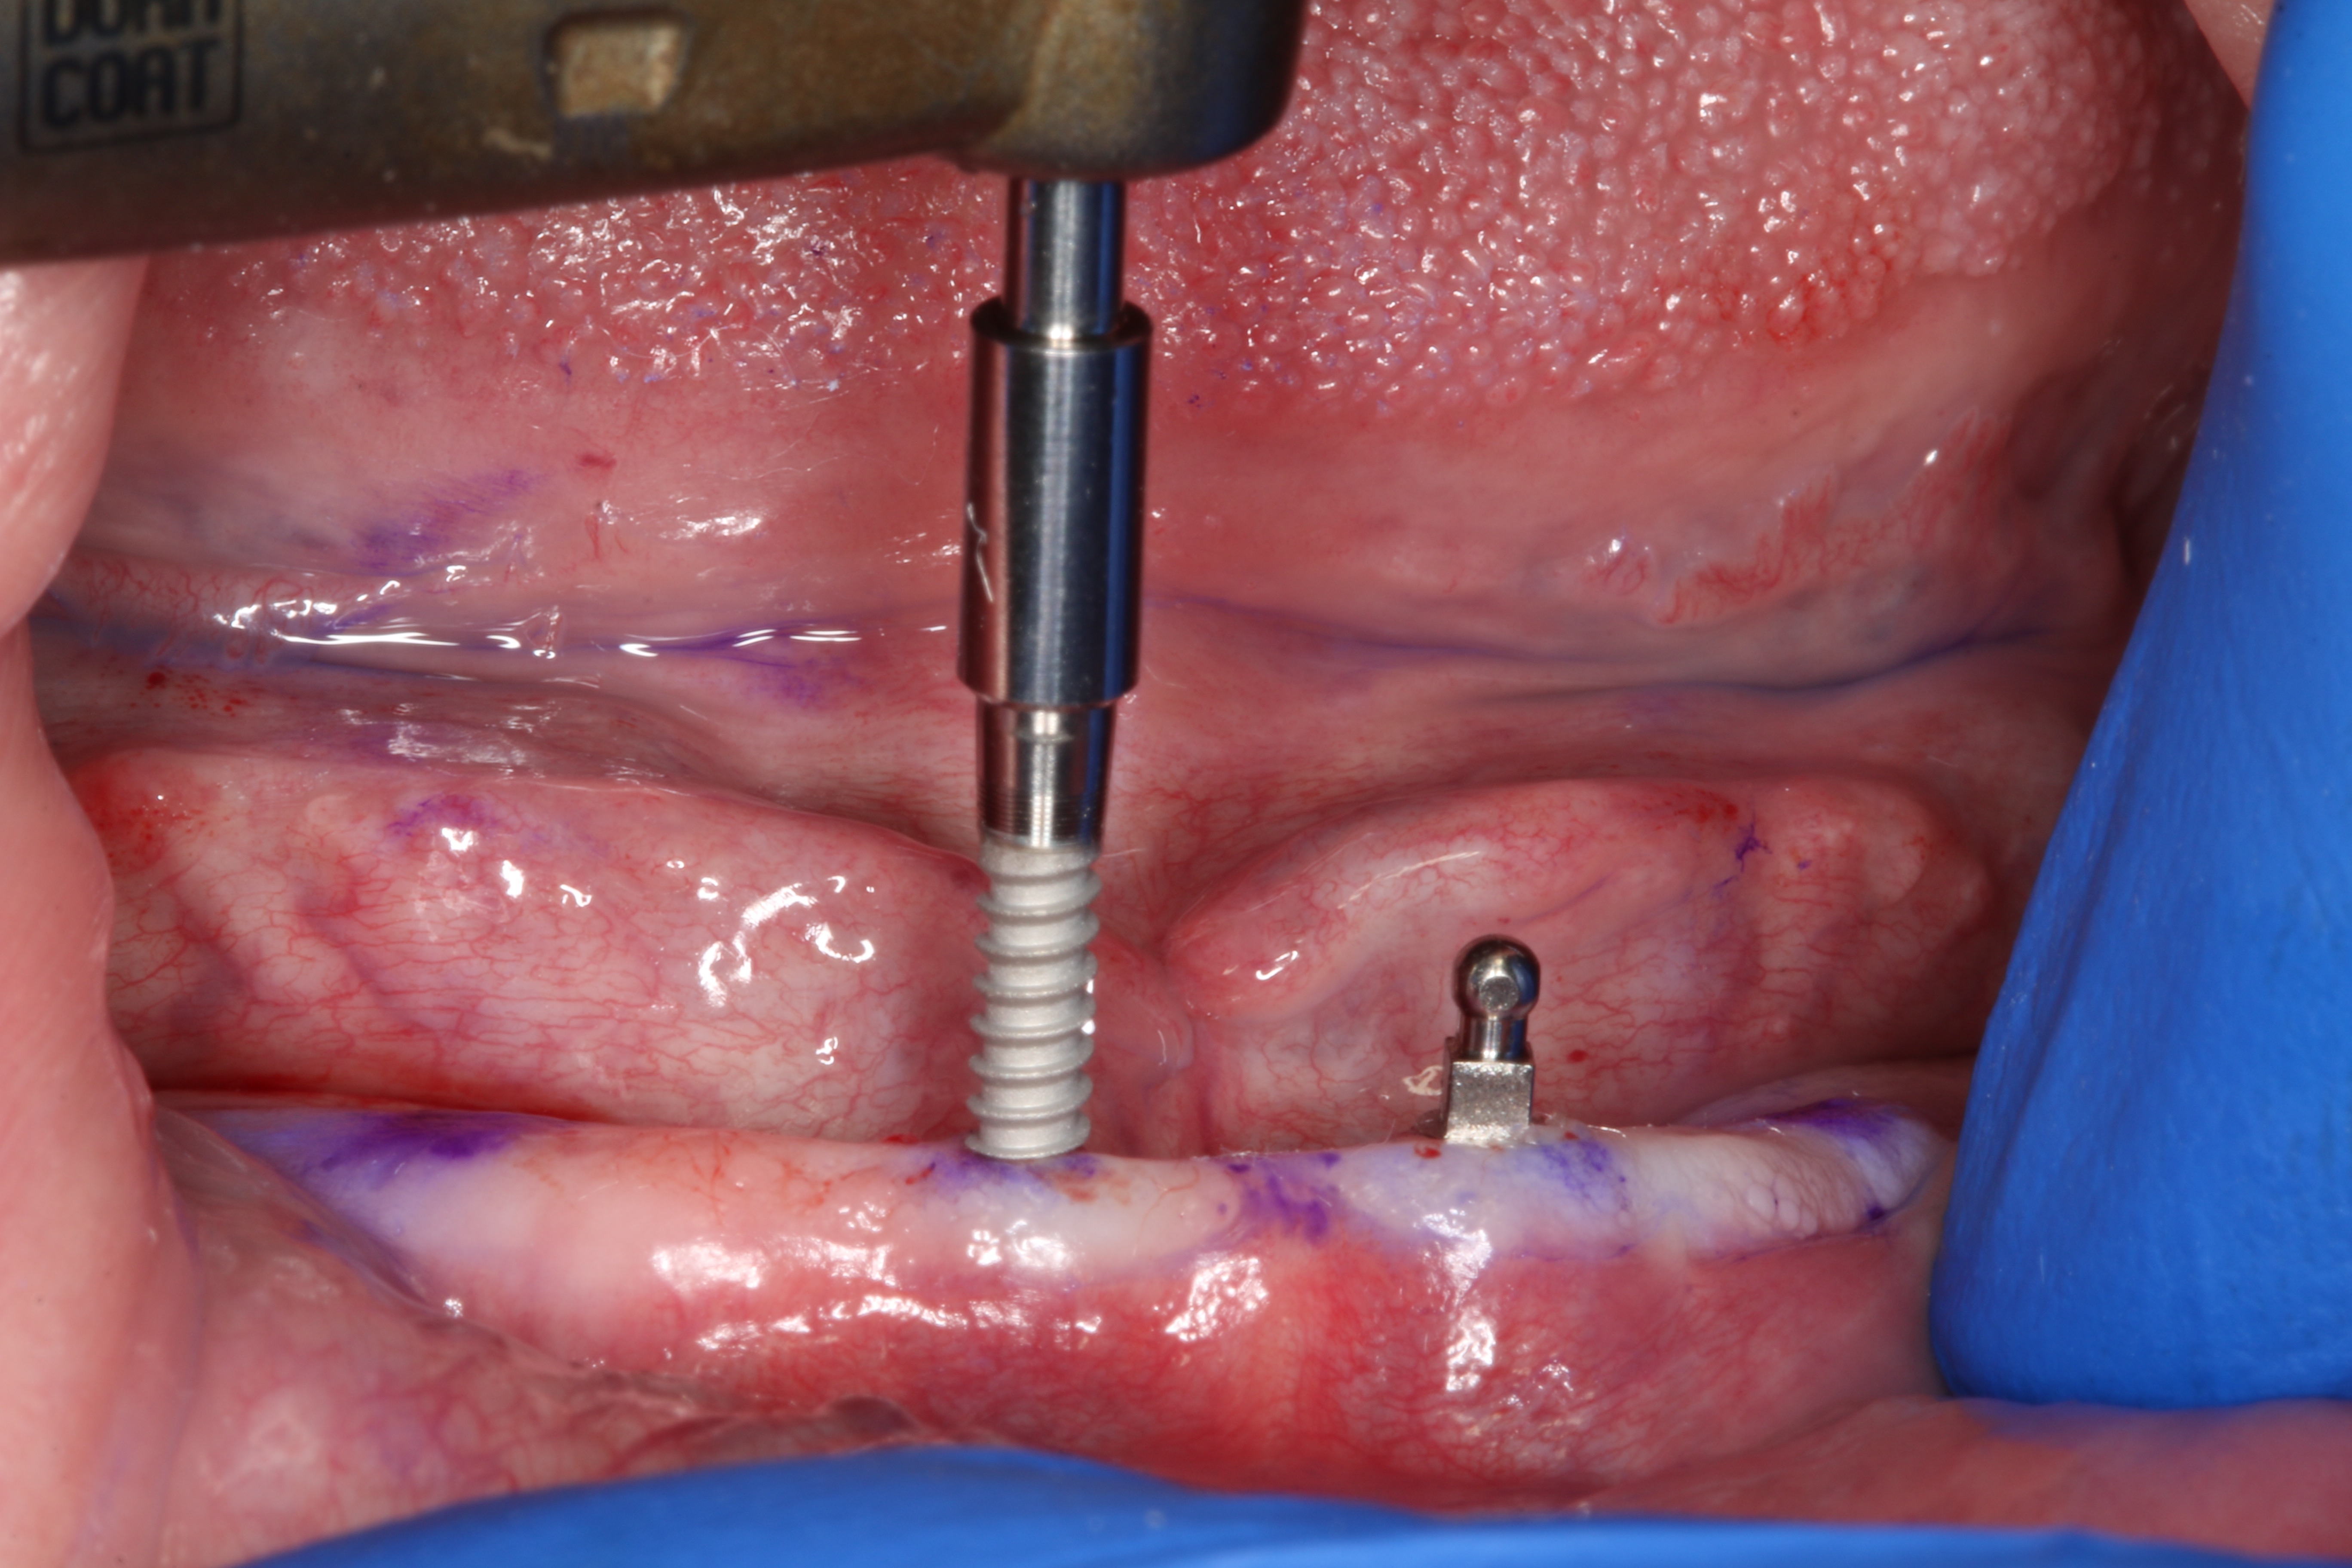

A surgical handpiece was used to perforate the mucosa and develop the osteotomy. The use of a transmucosal or “flapless” osteotomy is a well-established approach for the placement of narrow-diameter implants.22 If needed, as in the case of a surgical complication, a full-thickness mucoperiosteal flap can be developed, which will aid in visualizing the mandible. This requires great care so as not to disturb underlying structures. In this case a 1.2-mm-diameter twist drill running at 1200 rpm brought the osteotomy to a depth of 10 mm (Figure 3), which was dictated by the size of the selected implants. With practice, the clinician can create osteotomies that do not perforate the lingual or buccal cortical plates. This is done by assessing the vertical orientation of the bone by using a free hand to detect its buccal angulation. Interpreting the cross-sectional images is essential. If this is beyond the capabilities of the clinician or if the risk of perforation is great, a pre-drilled surgical guide of a flapped approach can be used for this step. Angulation pins or semi-inserted implants can be placed in shallow osteotomies to verify their orientation and check inter-implant parallelism.

Fig 3. Simplified “flapless” 1.2-mm-wide and 10-mm-deep osteotomy using surgical handpiece and copious irrigation at 1200 rpm. The underlying bone shape is felt with the non-dominant hand to guide handpiece angulation.

Figure 3